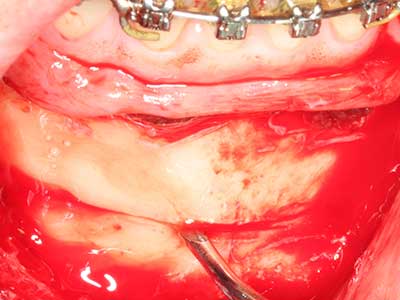

Fig. 28: During removal of metal, the basal chin regions are separated with the Piezomed while retaining the lingual blood supply.

Fig. 29: Forward displacement of the chin by 5 mm and fixation with two osteosynthesis plates (KLS Martin). The two mental nerves can be detected in the marginal region.

Fig. 30: The aesthetic improvement in the chin contour after the operation can be clearly seen.